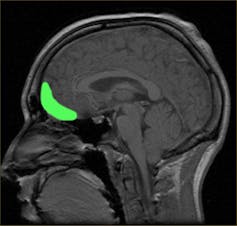

In 1848, 25-year-old Gage was working as a construction foreman for a railroad company. During the works, explosives were required to blast away rock. This intricate procedure involved explosive powder and a tamping iron rod. In a moment of distraction, Gage detonated the powder and the charge went off, sending the rod through his left cheek. It pierced his skull, and travelled through the front of his brain, exiting the top of his head at high speed. Modern day methods have since revealed that the likely site of damage was to parts of his prefrontal cortex.

All these cases have one thing in common: damage to areas of the prefrontal cortex, in particular the orbitofrontal cortex. Although they may be extreme examples, the idea that damage to these parts of the brain results in severe personality changes is now well-established. The prefrontal cortex has a role in managing behaviours, regulating emotions and responding appropriately. So it makes sense that disinhibited and inappropriate behaviour, psychopathy, criminal behaviour, and impulsivity have all been linked to damage of this area.